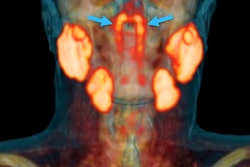

- Head and neck cancer (8.0%)

Indeterminate lesion on PET/CT classified by PET/MRI for 53-year-old man with lung cancer. Contrast-enhanced CT (A), PET (B), and fused F-18 FDG PET/CT (C) images are displayed in comparison with contrast-enhanced T1-weighted MRI (D), PET (E), and fused F-18 FDG PET/MRI (F) images. In CT (A), hyperdense, subcentimeter liver lesion (arrows) in segment VII is suggestive of transient hepatic attenuation difference or small hemangioma. As malignancy cannot be excluded, it needs further investigation. On PET/MRI, lesion is clearly classified as metastasis because of contrast enhancement and tracer uptake due to later acquisition time point. Follow-up CT confirmed diagnosis after 78 days. Image courtesy of the Journal of Nuclear Medicine.

Indeterminate lesion on PET/CT classified by PET/MRI for 53-year-old man with lung cancer. Contrast-enhanced CT (A), PET (B), and fused F-18 FDG PET/CT (C) images are displayed in comparison with contrast-enhanced T1-weighted MRI (D), PET (E), and fused F-18 FDG PET/MRI (F) images. In CT (A), hyperdense, subcentimeter liver lesion (arrows) in segment VII is suggestive of transient hepatic attenuation difference or small hemangioma. As malignancy cannot be excluded, it needs further investigation. On PET/MRI, lesion is clearly classified as metastasis because of contrast enhancement and tracer uptake due to later acquisition time point. Follow-up CT confirmed diagnosis after 78 days. Image courtesy of the Journal of Nuclear Medicine.After exclusions, the researchers examined 1,003 PET/MRI scans of 918 patients. PET/MRI outperformed PET/CT in terms of providing more tumor information (26.3%), mostly in patients with malignant bone disease, followed by lung cancer, prostate cancer, and gynecologic or breast cancer. PET/MRI identified additional malignant findings in 5.3% of cases, which lead to a change in tumor, node, and metastases (TNM) staging in 2.9% of cases. PET/MRI also clearly classified indeterminate PET/CT lesions in 11% of cases.